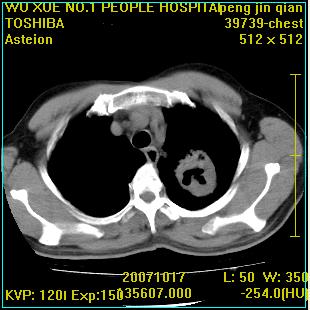

标题: CT10148:男,56岁,咳血。 [打印本页]

标题: CT10148:男,56岁,咳血。

左肺上叶尖段占位性病变,考虑肺癌.癌性空洞,并双肺转移灶及纵隔淋巴结转移

左肺上叶尖后段较大团块影,边缘光滑,内见不规则裂隙样空洞,周围明显见细小结节及渗出,与肺门方向结构紊乱,另:左上叶尖段外侧 舌叶内侧 右上叶尖段及下叶背段均见片状致密影。考虑:继发性肺结核伴空洞形成!

左上肺厚壁空洞影、两肺多发小片样不规则高密度灶。基本上能排除转移瘤。考虑肺结核伴空洞形成。

左上肺后壁空洞,内壁不规则,可见壁结节;左上叶尖段外侧 舌叶内侧 右上叶尖段及下叶背段均见片状致密影。考虑:左肺肺癌并两肺继发性肺结核?

左肺上叶尖后段较大团块影,边缘光滑,内见不规则裂隙样空洞,周围明显见细小结节及渗出,与肺门方向结构紊乱,另:左上叶尖段外侧 舌叶内侧 右上叶尖段及下叶背段均见片状致密影。考虑:继发性肺结核伴空洞形成!建议进一步检查,除外肺癌

右肺下叶背段/左上肺/左下肺结核伴空洞形成

结核 空洞伴两肺播散

浸润型肺结核伴左上肺空洞形成,两肺播散灶